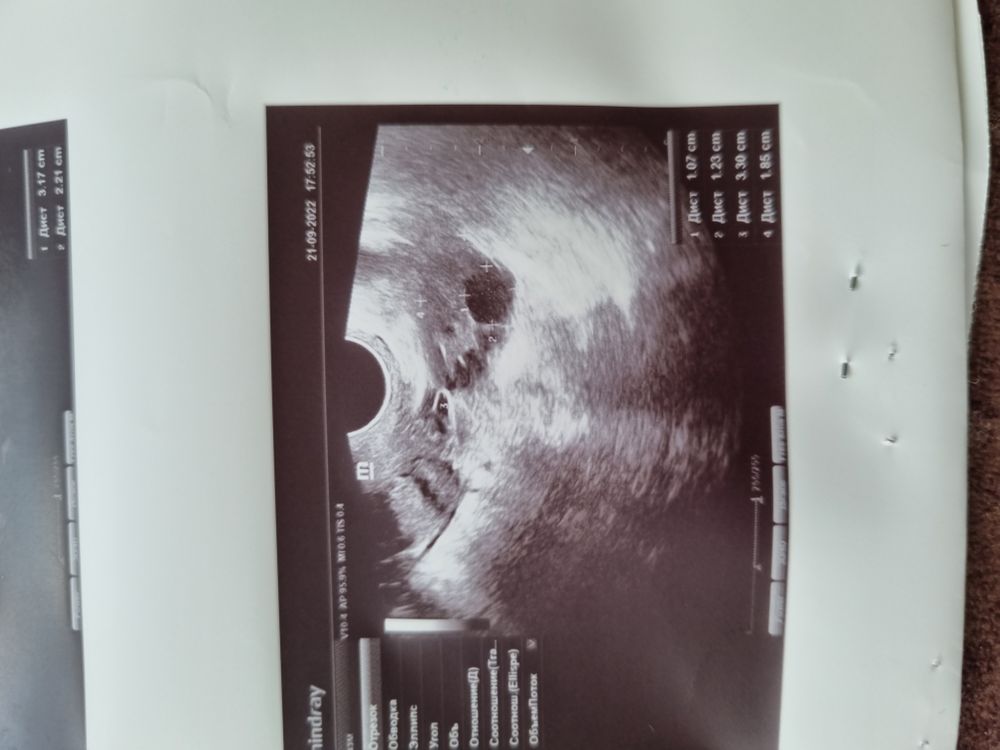

Пошла на УЗИ на 26дц, а там только ДФ, и тот небольшой 😭